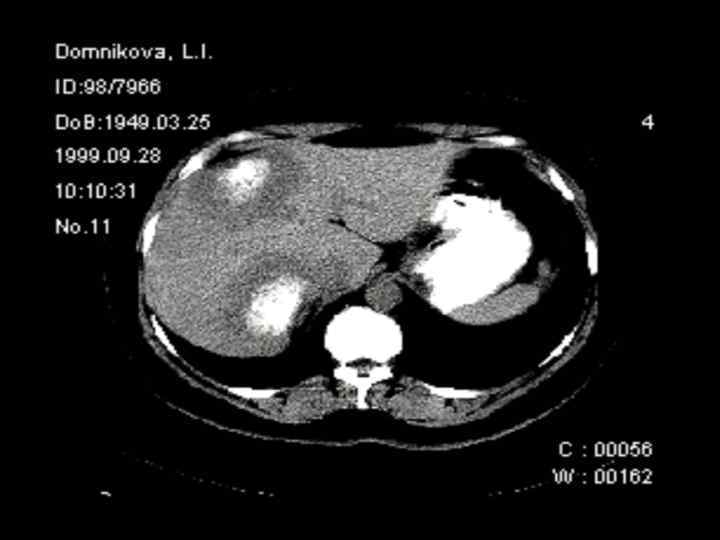

Методы диагностики опухолевой патологии печени. • • • УЗКТ Обследование по органам КТ с контрастированием МРТ с контрастированием Ангиография Пункционная биопсия Опухолевые маркеры (СА-19 -9, РЭА, АФП) Лапароскопия ПЭТ Лапаротомия с удалением опухолевого очага Динамическое наблюдение

Диагностические задачи 1. Являются ли выявленные изменения опухолью? 2. Какова природа опухоли: доброкачественная или злокачественная? 3. Точное указание пораженной доли печени. 4. Точное указание пораженного сегмента печени. 5. Имеется ли поражение ворот печени? 6. Инвазия в окружающие печень структуры. 7. Имеются ли внепеченочные метастазы?